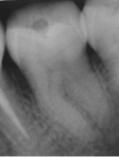

En 2013 concurre paciente de sexo femenino de 37 años de edad a la Clínica Integrada II UdelaR por caries profunda en pieza 37 (Fig. 2a). Se diagnostica CPPA ya que solo el test de fresado da positivo. Se planifica eliminación total de caries de paredes laterales con aislación absoluta. Se observa último test colorimétrico con rojo ácido 52 en propilenglicol (Detector, Pharma Dent, Uruguay) dejando fina capa de dentina infectada en pared axial (Fig. 2b) la cual se protege con mezcla de hidróxido de calcio (Ca(OH)2) puro con suero fisiológico y luego encima Ca(OH)2 fraguable (Life, Kerr, USA) (Fig. 2c). Se sella con ionómero vítreo (Gold Label Luting & Lining Cement, Tokyo, Japan).